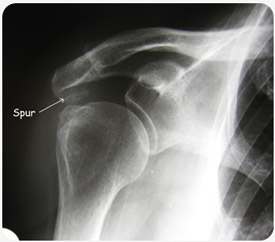

Ook kan de ruimte met de tijd nauwer worden door een slijtage proces met botaangroei aan de onderzijde van het schouder dak (acromion).

• Een klassieke radiografie geeft ons een eerste indruk van de afstand tussen het dak en de schouderbol (subacromiale ruimte).

Botspoor aan het acromion zichtbaar op anatomisch beeld Radiografie met botspoor aan het dak van de schouder Neer impingement test bij klinisch onderzoek van de schouder